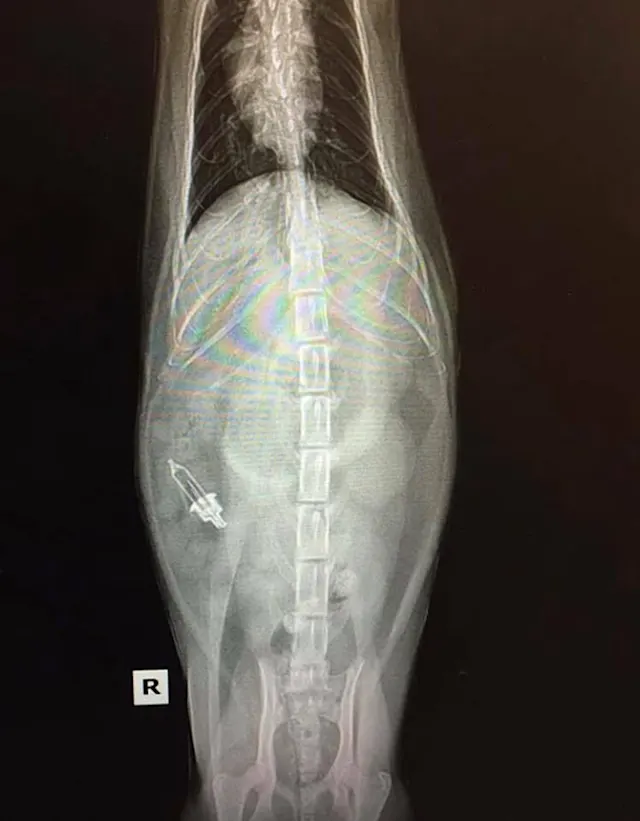

"This energetic 10-month-old Labrador swallowed a 12-inch serrated knife. The puppy was bouncing off the walls when he was brought in and it was hard to keep him still. Surgery went well and amazingly, nothing was damaged!"—Katelyn E